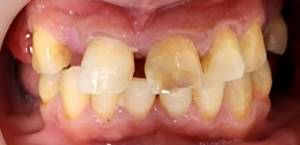

Intraoral Images: — (Before-treatment images)

• Teeth 8 and 9 were non-vital and distally rotated, with increased overjet and midline diastema

• Tooth 7 was missing

• Teeth 10 and 11 had large restorations

• Bilateral canine cusp tip attrition was present

• Multiple posterior teeth were missing: 1, 2, 3, 4, 5, 12, 13, 14, 15, 18, 19, 28, 29, 30, 31

• Reduced vertical dimension was observed